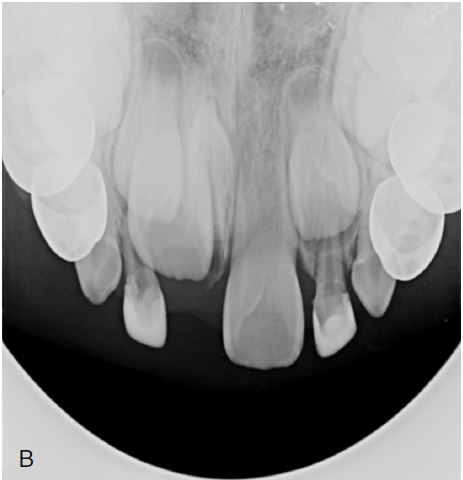

1. (Select ONE OR MORE correct answers)

The radiograph shows evidence of